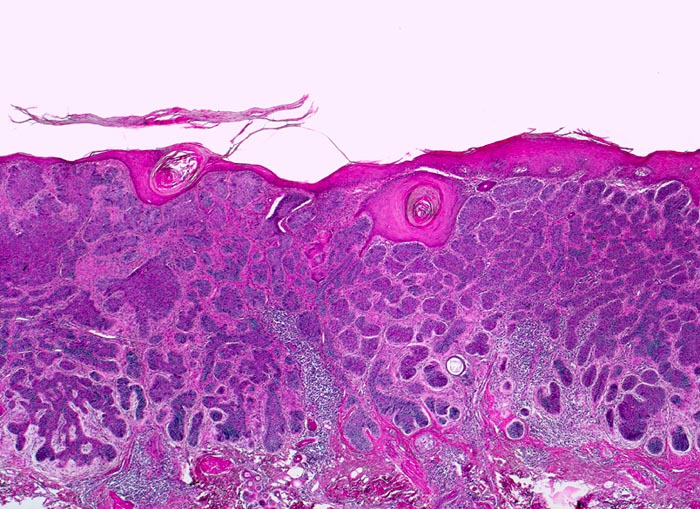

Morphologische Merkmale:

• Fokale oberflächliche Ulzeration bzw. Erosion der Epidermis über dem Tumor.

• Solide blaue Tumorzellplatten in der Dermis, teils mit Kontakt zur Epidermis.

• Die zytoplasmaarmen Tumorzellen ähneln Basalzellen der Epidermis.

• Palisadenförmige Anordnung der Tumorzellen am Rand der Zellplatten.

• Retraktionsartefakt zwischen Tumor und Stroma.

• Tumorstroma bestehend aus Fibroblasten, lockeren Kollagenfasern, hellblauen Muzineinlagerungen und chronischem Entzündungsinfiltrat.

• Im Zentrum einzelner Tumorzellplatten Verhornung, Tumornekrosen oder Hohlraumbildungen.

• Die Dermis in der tumorfreien Haut zeigt eine deutliche solare Elastose als Zeichen der chronischen UV Schädigung.